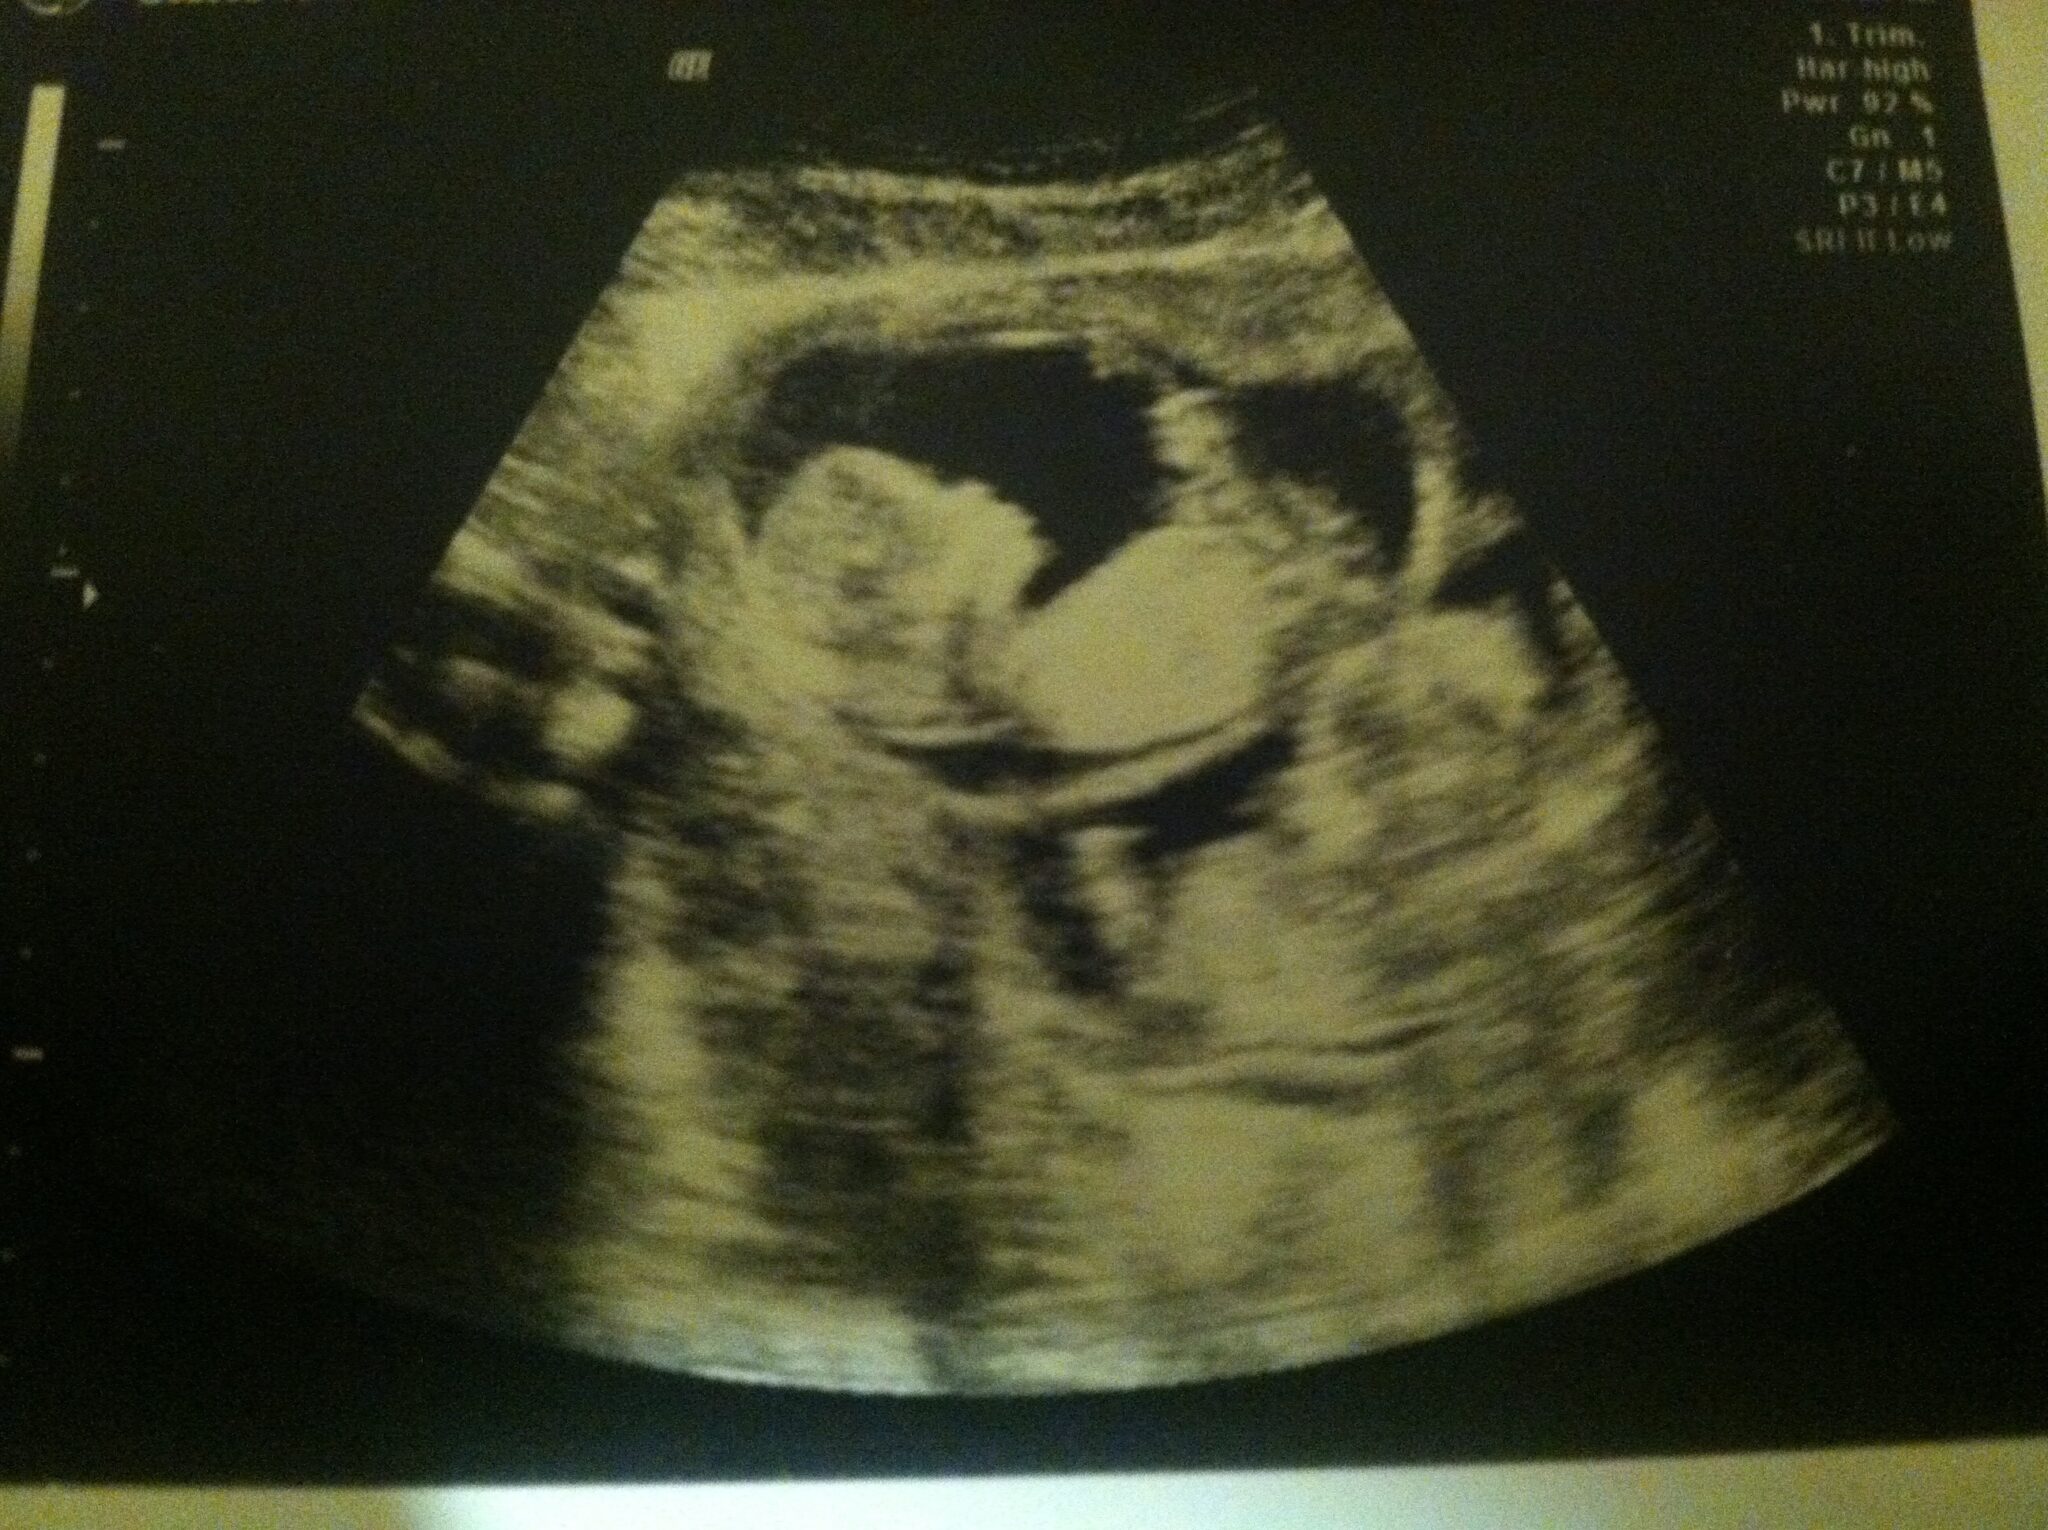

Ultrasound Photos at 12 Weeks Pregnant With Twins